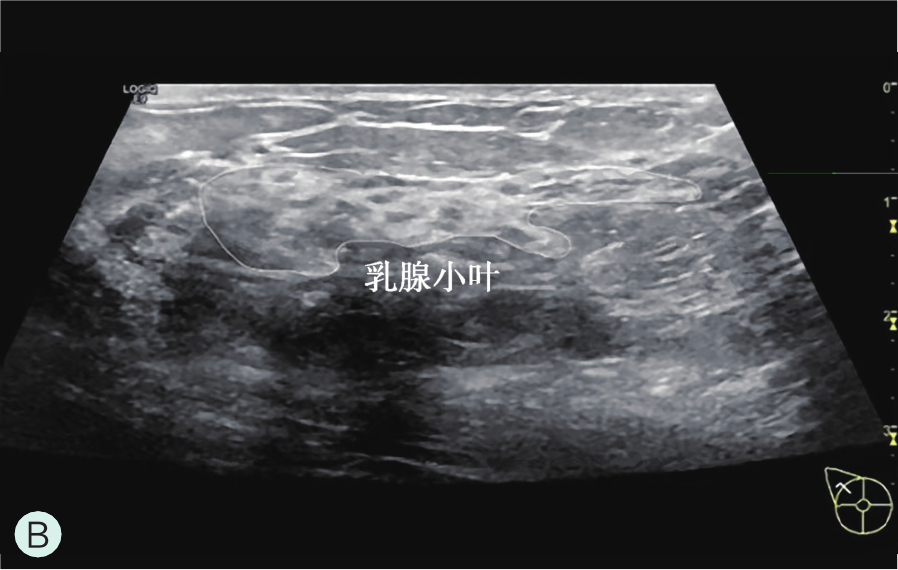

乳腺小叶为构成乳腺的基本单位,由乳腺末梢导管、腺泡和小叶间间质组成。此单位是乳腺功能的基础,每个乳腺由15~20个腺小叶导管系统组成,即15~20个乳腺叶组成。一个乳房所含乳腺叶数目是固定不变的,而小叶的数目和大小可以有很大变化。一般来说青年女性乳腺小叶数目多而且体积大,绝经后小叶明显萎缩。

图1-2-1 乳腺结构与影像图

A.乳腺模式图;B.乳腺小叶声像图;C、D.乳腺导管声像图;E.乳腺扩张导管MRI图